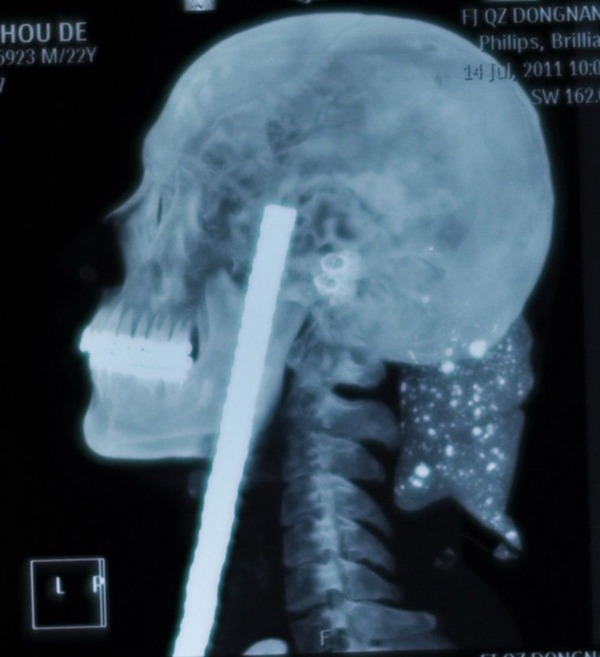

以前なんかで聞いた話だけど、米国で頭を鉄棒が貫通して

穴が開いた状態で運び込まれた人が居たそうだ。

その人はその後も生きてたそうだけど、人格が変わってしまったとか。

脳にダメージなければ意外と無事なのね